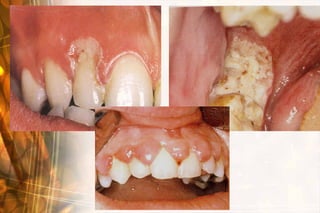

Consistency

   Bony hard: bone, cartilage, tooth structure